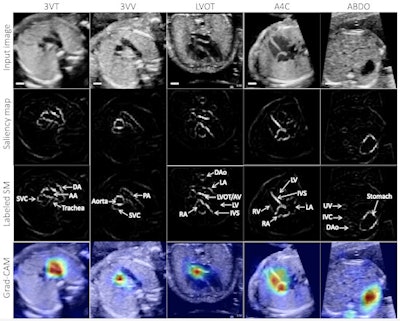

To help close this gap and improve the diagnosis of CHD in the community, the researchers trained neural networks to analyze the five axial screening views of the heart that have been specified in clinical guidelines as being able to detect CHD: 3-vessel trachea, 3-vessel view, apical-5-chamber, apical-4-chamber, and abdomen.

After training a convolutional neural network (CNN) to distinguish the five cardiac views of interest, the researchers then developed binary diagnostic classifiers to determine if each view was normal or abnormal. Next, these per-view diagnoses were used to create a composite diagnostic score as to whether the heart was normal or abnormal overall.